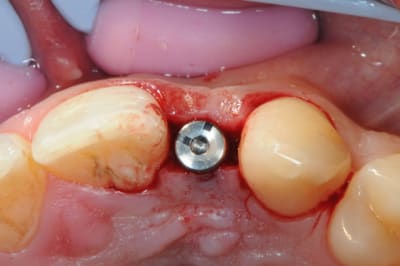

je reviens sur ce cas que j'ai un peu délaissé...

-cicatrisation

-mise en place vis de cica petit diamètre

-ensuite on augmente le diamètre en conservant et en gonflant les tissus gingivaux